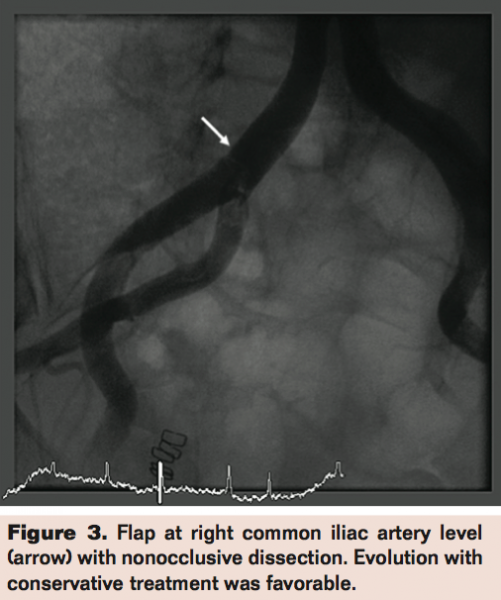

Minor vascular complications: Minor vascular complications occurred in 8 patients. In 5 patients, dissection of common or external iliac artery occurred without flow obstruction; expectant therapy was decided and clinical evolution was good (Figure 3). In 2 patients inguinal hematoma with favorable clinical evolution was observed. In one patient, failure of the Prostar XL sealing system occurred and it was treated with a Wallgraft stent implantation not requiring blood transfusion.